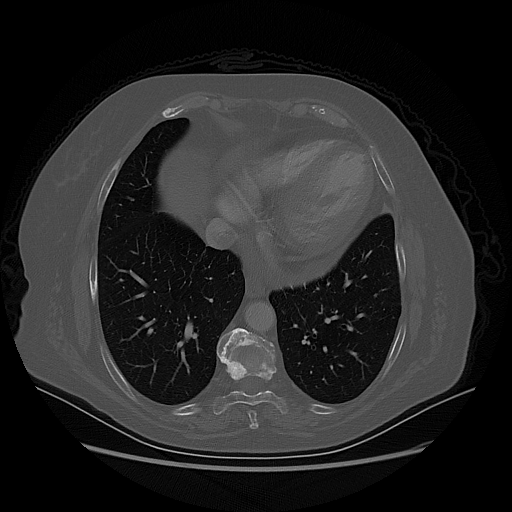

Generated VENOUS CT scan (A→B translation)

Full window (WL 1023.5, WW 4095 β†’ Low βˆ’1024, High +3071)

Lung window (WL -600, WW 1500 β†’ Low βˆ’1350, High +150)